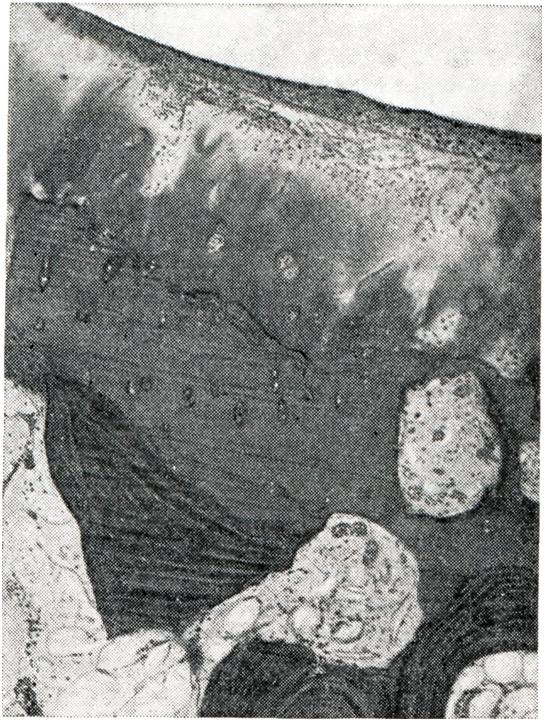

При микроскопии суставного хряща наблюдается его разволокнение, очаги некроза с образованием дефектов хрящевого покрытия и узурированием кости. Дефекты хряща замещаются грануляционной тканью, наползающей на суставную поверхность в виде различной толщины пленки (паннуса) — паннозный артрит. (рис. 2 и 3).

Рис. 2. | ||